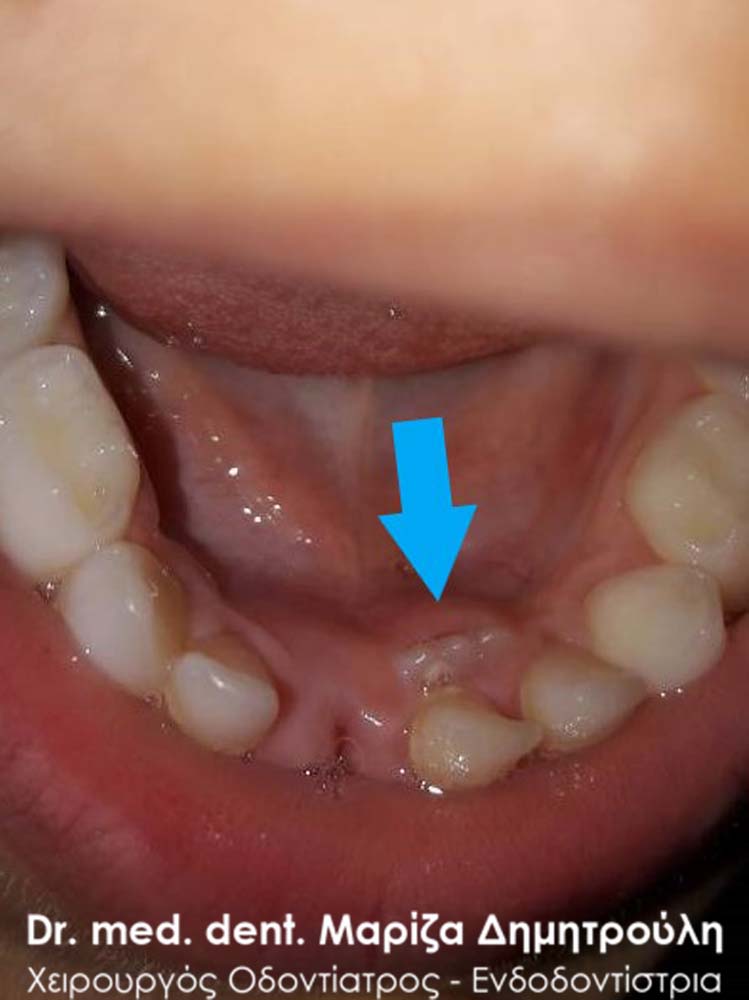

Στα δύο παρακάτω διαφορετικά περιστατικά παρατίθενται φωτογραφίες, όπου φαίνεται η παραμονή του νεογιλού κάτω κεντρικού τομέα παρόλο που στο στόμα των μικρών ασθενών είχε ήδη ανατείλει το αντίστοιχο μόνιμο δόντι. Στην προκειμένη περίπτωση το παιδικό δόντι αφαιρείται από τον οδοντίατρο, ώστε το μόνιμο δόντι με τη βοήθεια της γλώσσας να πάρει την τελική του θέση μέσα στο στόμα του παιδιού.